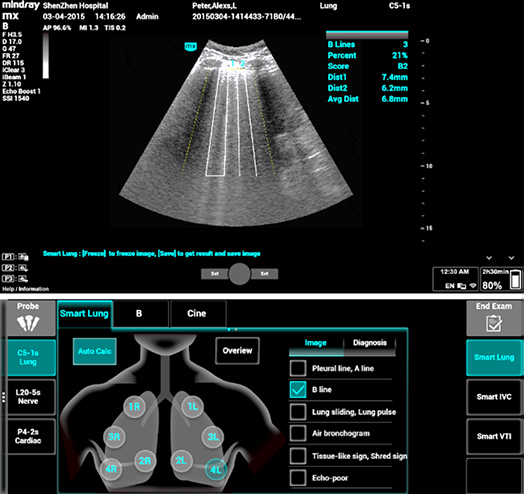

1Smart B-line

Automatically count the number of B-lines and percentage of area of B-lines according to the protocols. And score the performance of lung in four patterns according to lung aeration. Image overview and color map of score can assist on the assessment of pulmonary function.